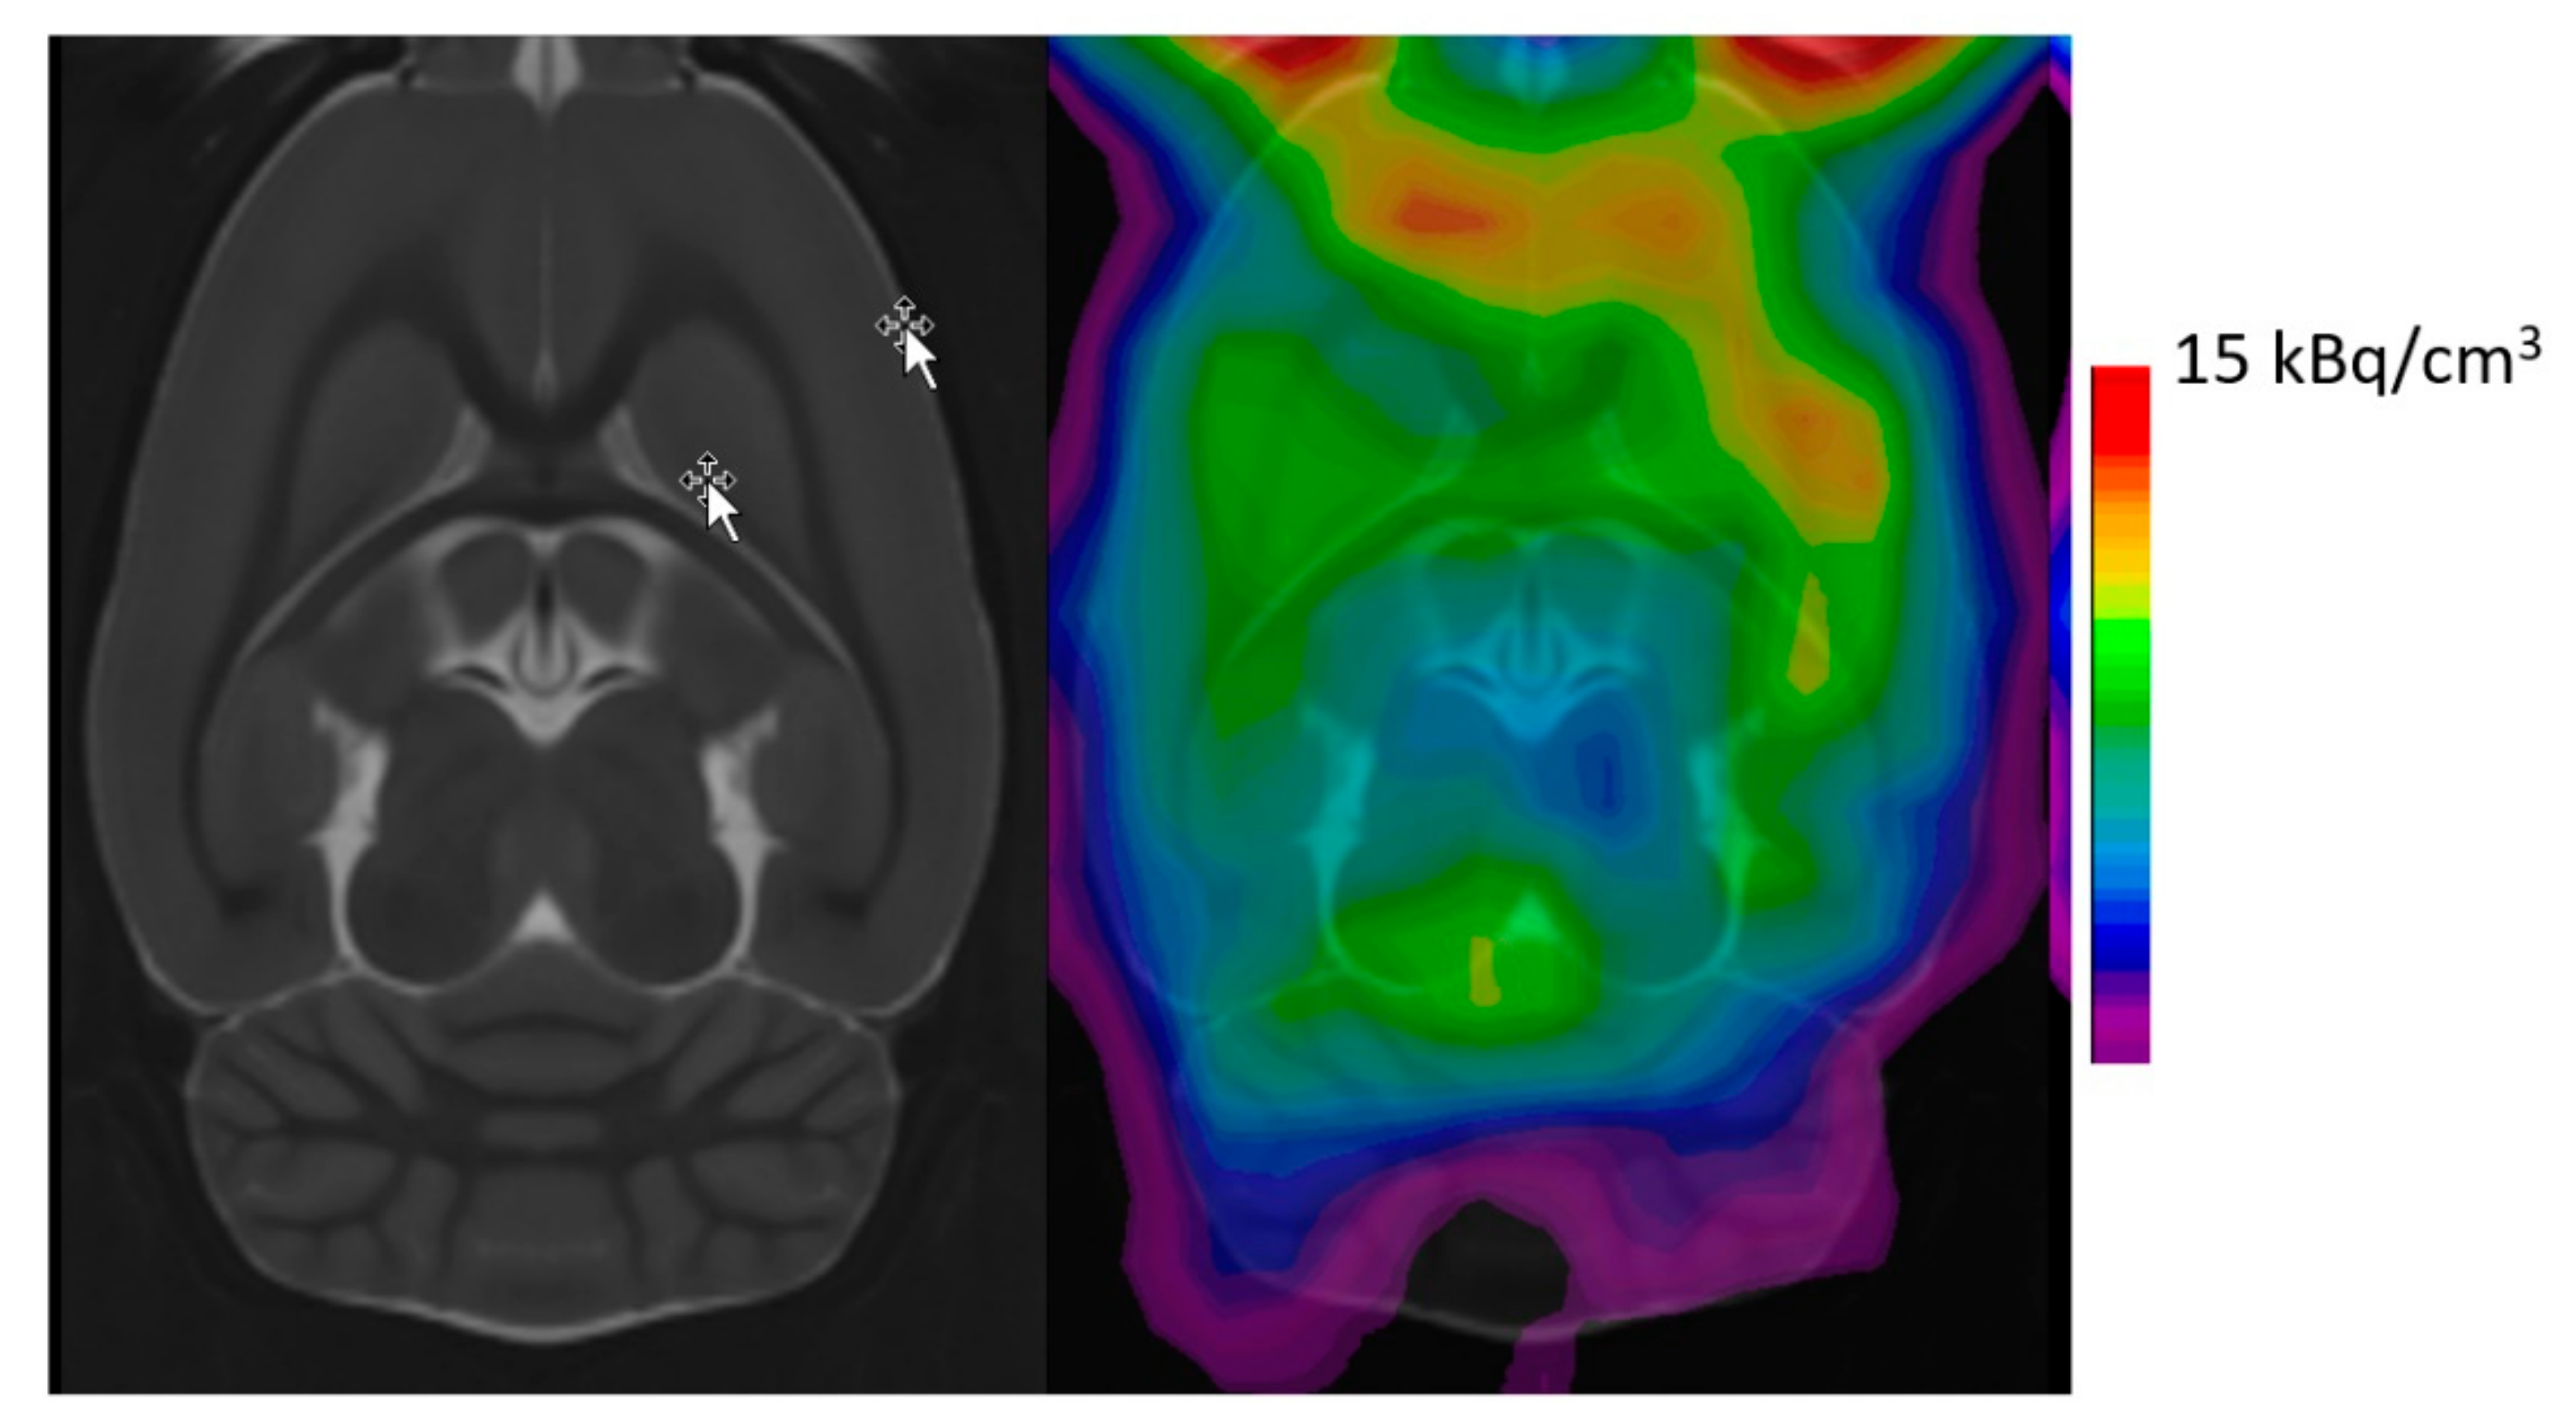

- Ettrup, A.; Palner, M.; Gillings, N.; Santini, M.A.; Hansen, M.; Kornum, B.R.; Rasmussen, L.K.; Nagren, K.; Madsen, J.; Begtrup, M.; et al. Radiosynthesis and evaluation of 11C-CIMBI-5 as a 5-HT2A receptor agonist radioligand for PET. J. Nucl. Med. 2010, 51, 1763–1770. [Google Scholar] [CrossRef] [PubMed]

- Prabhakaran, J.; DeLorenzo, C.; Zanderigo, F.; Knudsen, G.M.; Gilling, N.; Pratap, M.; Jorgensen, M.J.; Daunais, J.; Kaplan, J.R.; Parsey, R.V.; et al. In vivo PET Imaging of [11C]CIMBI-5, a 5-HT2AR Agonist Radiotracer in Nonhuman Primates. J. Pharm. Pharm. Sci. 2019, 22, 352–364. [Google Scholar] [CrossRef]

- Ettrup, A.; Hansen, M.; Santini, M.A.; Paine, J.; Gillings, N.; Palner, M.; Lehel, S.; Herth, M.M.; Madsen, J.; Kristensen, J.; et al. Radiosynthesis and in vivo evaluation of a series of substituted 11C-phenethylamines as 5-HT (2A) agonist PET tracers. Eur. J. Nucl. Med. Mol. Imaging 2011, 38, 681–693. [Google Scholar] [CrossRef] [PubMed]

- Ettrup, A.; Svarer, C.; McMahon, B.; da Cunha-Bang, S.; Lehel, S.; Moller, K.; Dyssegaard, A.; Ganz, M.; Beliveau, V.; Jorgensen, L.M.; et al. Serotonin 2A receptor agonist binding in the human brain with [(11)C]Cimbi-36: Test-retest reproducibility and head-to-head comparison with the antagonist [(18)F]altanserin. NeuroImage 2016, 130, 167–174. [Google Scholar] [CrossRef] [PubMed]

- Finnema, S.J.; Stepanov, V.; Ettrup, A.; Nakao, R.; Amini, N.; Svedberg, M.; Lehmann, C.; Hansen, M.; Knudsen, G.M.; Halldin, C. Characterization of [(11)C]Cimbi-36 as an agonist PET radioligand for the 5-HT(2A) and 5-HT(2C) receptors in the nonhuman primate brain. NeuroImage 2014, 84, 342–353. [Google Scholar] [CrossRef]

- Jorgensen, L.M.; Weikop, P.; Villadsen, J.; Visnapuu, T.; Ettrup, A.; Hansen, H.D.; Baandrup, A.O.; Andersen, F.L.; Bjarkam, C.R.; Thomsen, C.; et al. Cerebral 5-HT release correlates with [(11)C]Cimbi36 PET measures of 5-HT2A receptor occupancy in the pig brain. J. Cereb. Blood Flow Metab. 2017, 37, 425–434. [Google Scholar] [CrossRef]